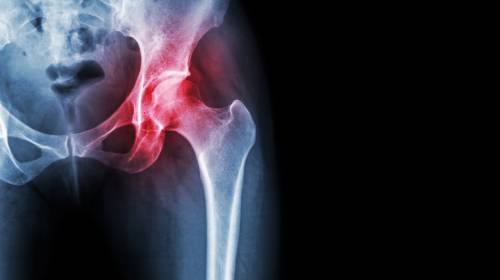

髖關(guān)節(jié)炎是如何引起的?【廣東高尚醫(yī)學(xué)影像】

髖關(guān)節(jié)屬于杵臼關(guān)節(jié),是由股骨頭和髖臼相對(duì)構(gòu)成,多為軸性關(guān)節(jié),能作屈伸、收展、旋轉(zhuǎn)等運(yùn)動(dòng),但由于關(guān)節(jié)頭和關(guān)節(jié)窩之間的面積差不大,運(yùn)動(dòng)范圍較小,且關(guān)節(jié)囊較厚,限制關(guān)節(jié)運(yùn)動(dòng)幅度的韌帶又比較有力,因此髖關(guān)節(jié)雖有強(qiáng)穩(wěn)固性,但靈活性卻較差,因此在髖關(guān)節(jié)運(yùn)動(dòng)時(shí),若有外力作用于膝關(guān)節(jié),就容易導(dǎo)致髖關(guān)節(jié)后脫位。當(dāng)髖關(guān)節(jié)面長期負(fù)重不均衡,關(guān)節(jié)軟骨就會(huì)產(chǎn)生變性(或產(chǎn)生骨質(zhì)結(jié)構(gòu)改變),這就是髖關(guān)節(jié)炎。

X線篩查對(duì)髖關(guān)節(jié)炎的判斷:

1. 早期影像顯示髖關(guān)節(jié)周圍軟組織腫脹,密度增加,關(guān)節(jié)間隙增寬。

2. 中期影像顯示為關(guān)節(jié)軟骨遭破壞,關(guān)節(jié)間隙變窄,關(guān)節(jié)面骨質(zhì)出現(xiàn)糜爛破壞。

3. 后期影像顯示化膿病變從關(guān)節(jié)囊韌帶附著處入侵骨內(nèi),骨內(nèi)形成膿腫。